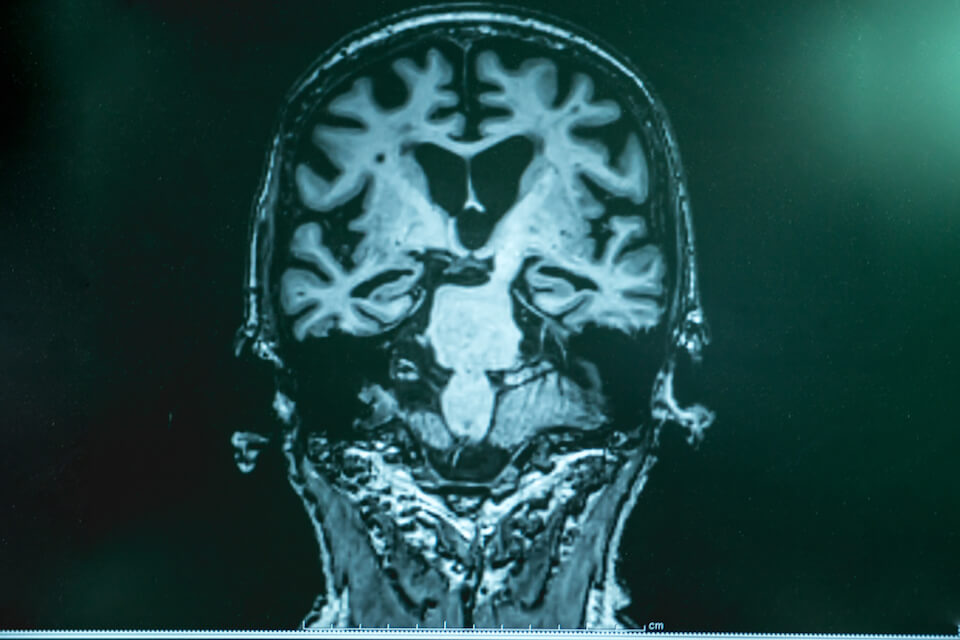

Dr James Everett, Postdoctoral Research Associate at Keele University and a lead author on the paper, said: “Should the magnetic metals identified through this research be linked to the development of Alzheimer’s, they have a potential use as markers for disease diagnosis using techniques such as magnetic resonance imaging (MRI), allowing for pre-clinical disease screening of at-risk cohorts.”